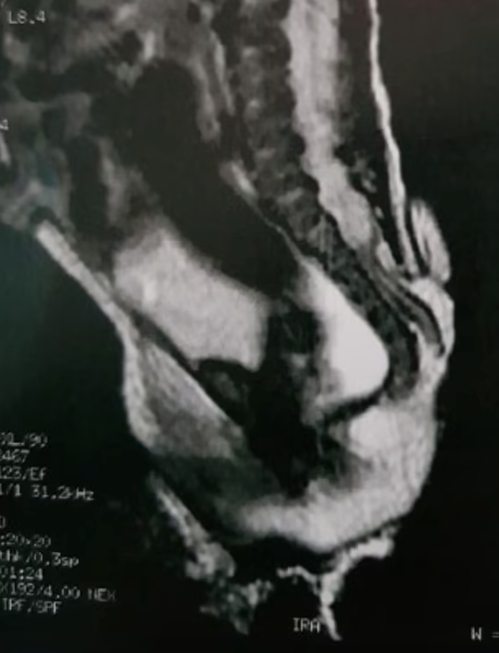

女嬰的主治醫師提到,她出生時患有脊柱裂,導致脊柱出現縫隙,推測為長出「尾巴」的原因,發生於孕婦子宮。

對此,聖保羅兒童醫院醫師解釋,該附肢是「人類的假尾巴」,為脊椎問題或腫瘤所引起,並非真正的尾巴,因為真正的尾巴是由肌肉及神經血管組成,但沒有骨頭。